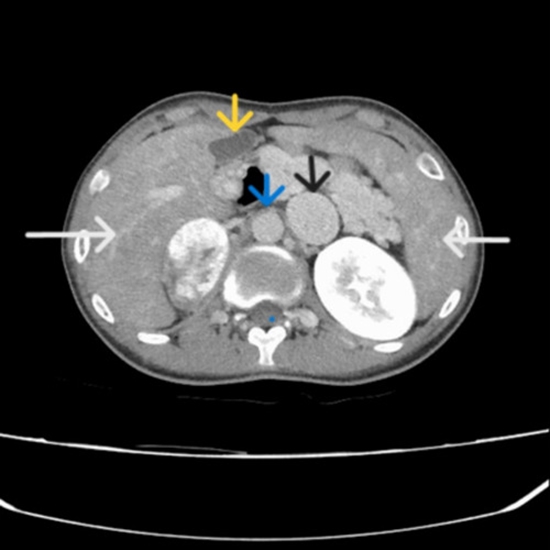

A 19-year-old male with congenital heart disease was incidentally found to have a right adrenal mass during abdominal ultrasonography which followed abnormal lab results. Computed tomography (CT) scans confirmed abnormal organ positioning consistent with heterotaxy syndrome, including a midline liver, right-sided colon, and the absence of a spleen in its typical location. Subsequent scintigraphy with Technetium-99 m denatured red blood cells revealed a functioning ectopic spleen in the left subdiaphragmatic space. The right adrenal mass was confirmed to be pheochromocytoma based on elevated urinary catecholamine levels. Despite recommendations for surgery, the patient chose medical management with alpha-blockers and remained stable over a one-year follow-up with no significant events.

This case is notable concurrency of pheochromocytoma and heterotaxy and for the rare occurrence of a functioning ectopic spleen in a patient with heterotaxy syndrome, a condition where splenic anomalies typically manifest as asplenia or polysplenia. The importance of extensive imaging, particularly Tc-99 m labeled denatured erythrocyte scintigraphy imaging, is emphasized, as routine imaging like CT scans may fail to detect ectopic organs. Additionally, the concurrent presence of pheochromocytoma (PCC) and heterotaxy syndrome, although rare, raises intriguing questions about their potential link. While this case does not explore the association in detail, chronic hypoxia caused by congenital cardiovascular anomalies in heterotaxy syndrome could activate hypoxia-inducible factors (HIFs), which may promote tumorigenesis, including the development of PCC. Future studies are warranted to explore these mechanisms further and clarify the pathophysiological connection between heterotaxy syndrome, hypoxia, and PCC.